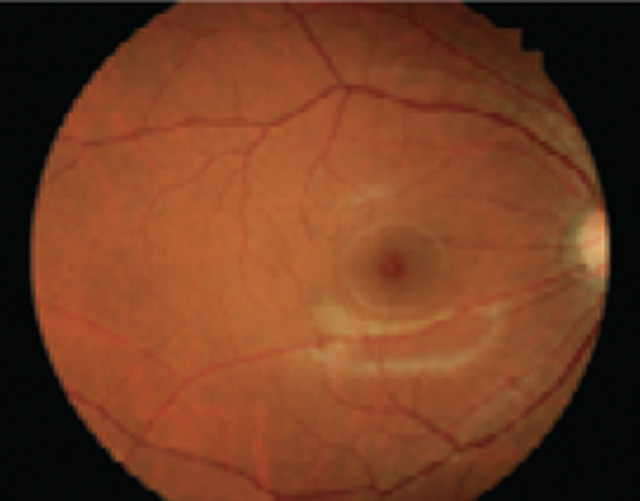

The Kowa nonmyd 7 is an easy-to-use fundus camera featuring 24 megapixel, high resolution photography.

Sharper, clearer images guarantee better clinical decisions.

The Nonmyd 7 is a high quality, simple to use digital retinal camera built with traditional Kowa reliability. Capture high levels of clinical detail with the sharp and clear images of the latest Nikon® digital camera. A choice of optical magnifications offers the standard 45° view or a 20° view for enhanced detail. A choice of fixation modes offers three standard positions while the optional external fixation target allows the user to choose the position on the retina. The industry standard USB interface connects to a desktop or laptop PC and the included Portable VK-2 digital imaging software lets you store, view, and compare your images with ease.